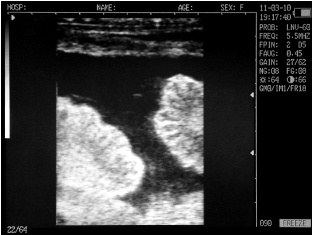

Endometritis in the uterus of the cow